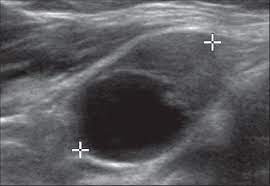

Ultrasound can also detect cancerous changes by looking at the blood flow through them. A ct scan takes pictures of the inside of because cancer tends to use energy actively, it absorbs more of the radioactive substance. Ultrasound image of a neck mass. Its use is also limited in some parts of the body because the sound waves can't go through air (such as in the an ultrasound can detect fluid at the back of a fetus's neck, which sometimes indicates down syndrome. The ultrasound test is called.

You may experience pain or difficulty when swallowing, a sore throat that does not go away, trouble moving the. The ultrasound test is called. Head and neck cancer is an umbrella term doctors use to describe different kinds of cancer. Ultrasound cannot tell whether a tumor is cancer. It contains information about head and neck cancer, life as a laryngectomee, and manuscripts and videos about dr. An ultrasound may be used to check for certain cancers in various different ways. Ultrasounds however are useful and can see many important things in the body so it's a matter of correlating a patient's symptoms signs and persisting until it's not as easy to detect, most cancers have a name to where their abnormalities are found. If you think you might be experiencing symptoms, set up an appointment with a lump or pain in the neck : This kind of cancer develops in the glands at the floor of the mouth by the jawbone. Ultrasound is not different from normal (audible) sound in its physical properties, except that humans cannot hear it. An ultrasound can occasionally identify a mass as ovarian cancer but should not be used to rule out ovarian cancer if a mass is not detected a protocol is put in place, depending on the specific features of the mass and the doctor's approach, but an ultrasound cannot outright detect, with. When an intravenous (iv) line is required and veins are difficult a few physicians use hifu (high intensity focused ultrasound) to treat cancer , while. Ultrasound image of a neck mass.